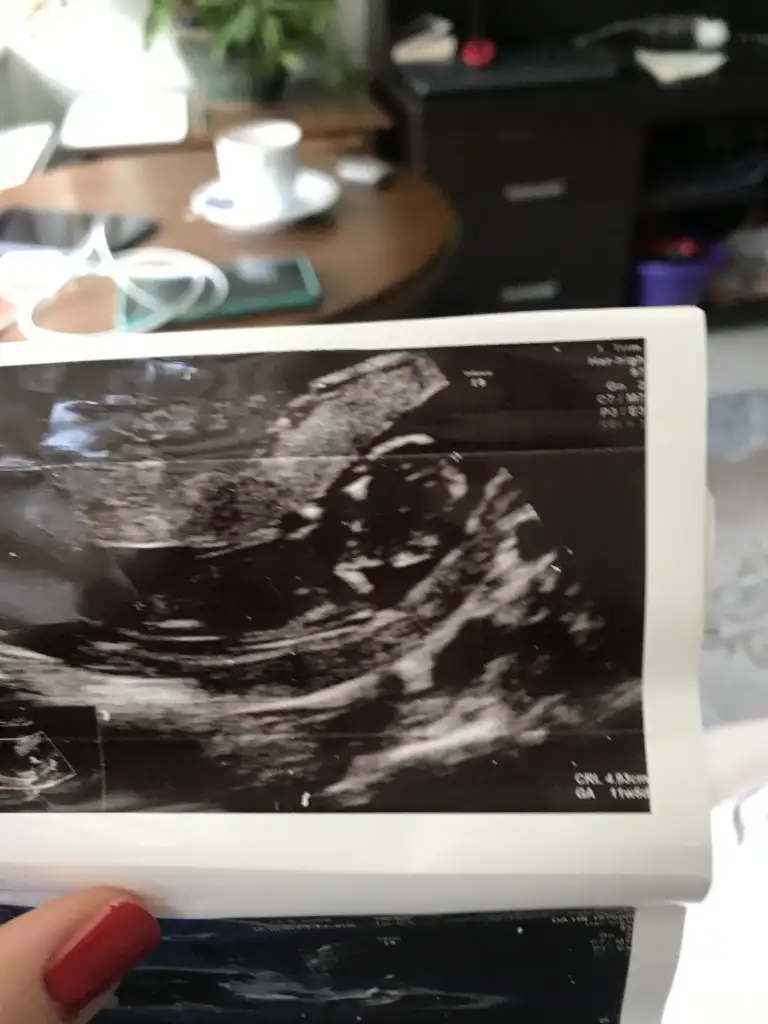

Hemen göndereyim olması lazımdıBunlar var birde videodan aldığım bir görüntü vardıEki Görüntüle 2596225 Eki Görüntüle 2596225 Eki Görüntüle 2596226 Eki Görüntüle 2596227